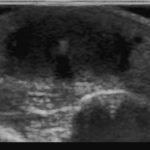

X-rays of the foot were obtained and no radiopaque foreign body was visualized. Due to high clinical suspicion for retained foreign body, a point-of-care ultrasound was performed by applying a high-frequency linear probe at the area of discomfort. In the long axis an ovoid focus of hypoechogenicity (orange outline) is visualized. Within this finding there is a linear focus (yellow line) of increased echogenicity measuring 1 mm in diameter and 1 cm in length. On short axis view, a rectangle focus (green dot) demonstrating shadowing (blue highlight) is seen.